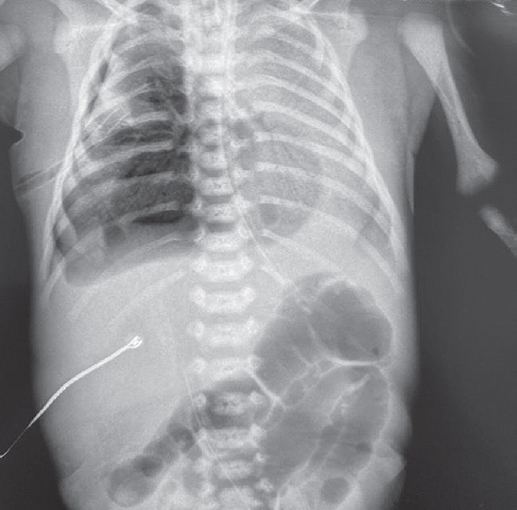

В статье представлен случай успешного лечения острого респираторного дистресс-синдрома у доношенного новорожденного, осложнившегося баротравмой легких, с применением монобронхиального введения экзогенного сурфактанта под рентгенологическим контролем. С целью оценки течения заболевания и эффективности лечения проведен ретроспективный анализ медицинской документации. С первых минут жизни у ребенка отмечались дыхательные расстройства, что стало основанием для проведения неинвазивной искусственной вентиляции легких. В динамике выявлено прогрессирование гиперкапнии и гипоксемии, в связи с чем была выполнена интубация трахеи и начата конвекциональная искусственная вентиляция легких с FiO2 = 1,0. Ключевой элемент терапии, позволивший достичь стабилизации состояния и регрессирования нарушений газообмена с полным выздоровлением пациента, — монобронхиальное введение экзогенного сурфактанта.

Монобронхиальное введение сурфактанта при остром респираторном дистресс-синдроме с гетерогенным поражением легких является эффективным вариантом лечения и может использоваться в клинической практике при рефрактерной гипоксемии.